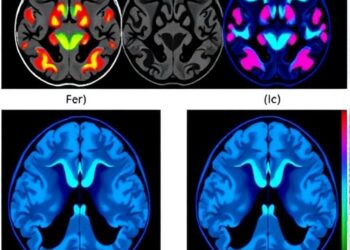

A groundbreaking study has emerged from the University of Nevada, Reno, revealing promising insights into the treatment of glioblastoma multiforme ...